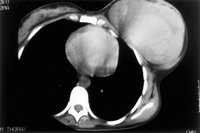

PHYLLODES TUMORS ARE RARE fibroepithelial neoplasms that account for 0.3 to 1 per cent of all breast cancers in females. The term cystosarcoma phyllodes was coined by Johannes Muller in 1838 to describe the gross appearance of this "cystic, fleshy, leafy, tumor of the breast," which he clearly stated to be a benign tumor. Lee and Pack reported the first case of metastatic phyllodes tumor in 1931. Since then, metastatic disease has been noted to occur to the lung, pleura, axial skeleton, central nervous system, pancreas, duodenum, thigh, sacrum, and mandible.. The term cystosarcoma implies a relationship to cystic disease and tends to overstate the malignant potential of this lesion. Thus, cystosarcoma phyllodes is now felt to be a misnomer, and the World Health Organization now classifies this breast neoplasm as a phyllodes tumor (PT). (Breast sarcomas often appear quite large, see pic of angiosarcoma of breast and CT of the breast.)